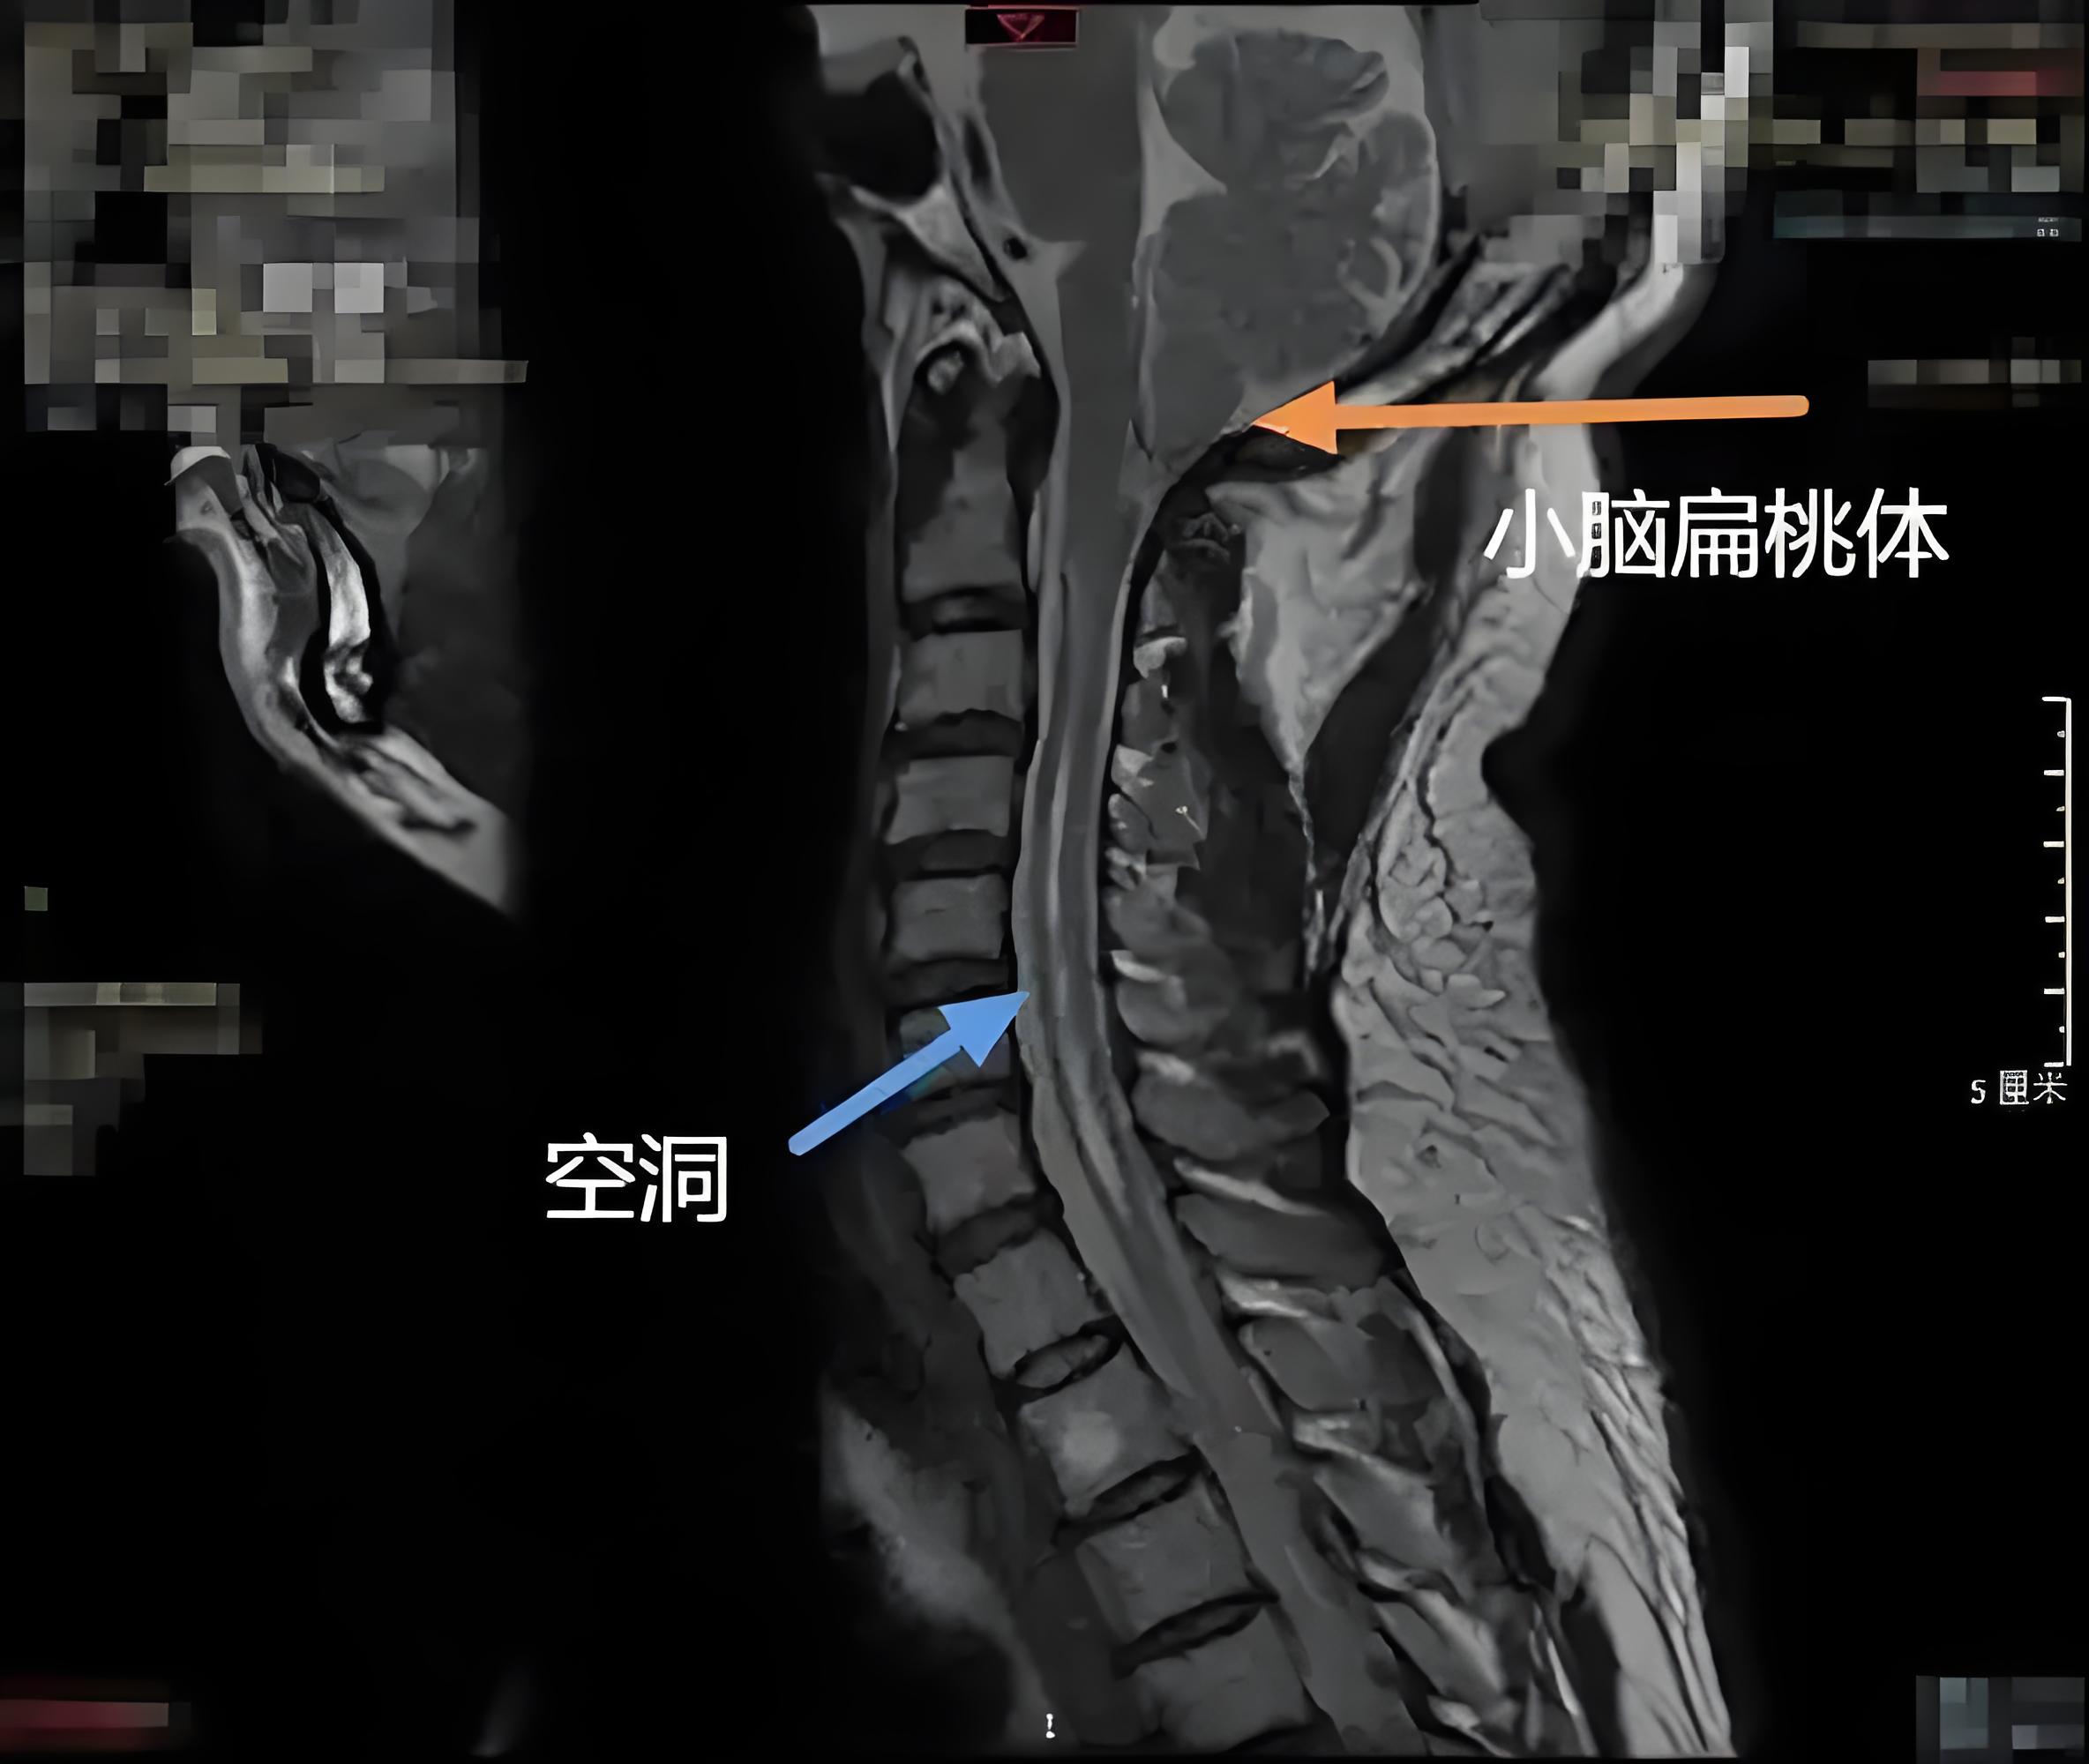

脊髓空洞症的病因有多种,最常见的为小脑扁桃体下疝寰枕交界部畸形引起的颈髓和上胸髓空洞,这主要是因为下疝的小脑扁桃体充满后颅窝和枕大池,造成颅腔内与蛛网膜下腔脑脊液压力分离,从而引起脑脊液循环和吸收障碍,最终形成脊髓空洞此外,慢性脊髓蛛网膜炎脊髓内肿瘤如室管膜瘤星形。

脊髓空洞症的治疗需要综合中西医疗法,才能达到最佳效果该病多因小脑扁桃体下疝导致脊髓中央管扩张,引发脊髓生理畸形,从而损伤脊髓并导致神经功能麻痹,症状包括损伤脊髓平面以下的运动感觉知觉痛温觉减退等肢体功能障碍如果病情正在继发过程中,可采用手术分流减压,预防脊髓神经继发损害加重如伴有脑。